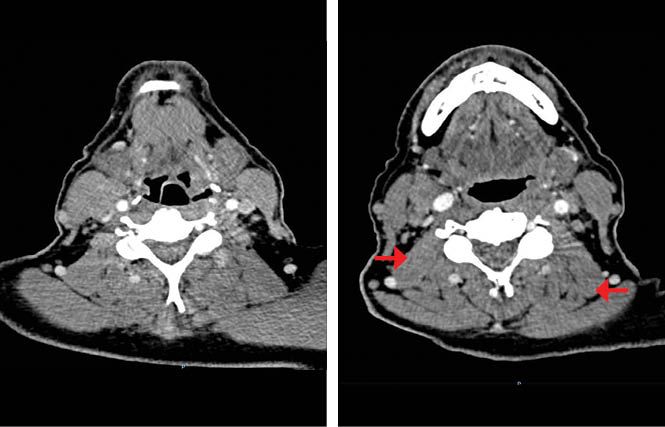

Our patient began induction chemotherapy based on the TPF regimen. He received 2 cycles and experienced grade 2 toxicities that did not require treatment delays. A subsequent CT scan indicated decreases of the primary tumor and the cervical matted nodes, equivalent to a PR with a greater than 50% reduction in tumor size (Figure 1b).

Figure 1B. Post induction chemotherapy (IC) contrast enhanced CT scan shows a partial response of the tumor located in the hypopharynx (left). Decrease in size of the right matted lymph nodes and the left lymph nodes (right).